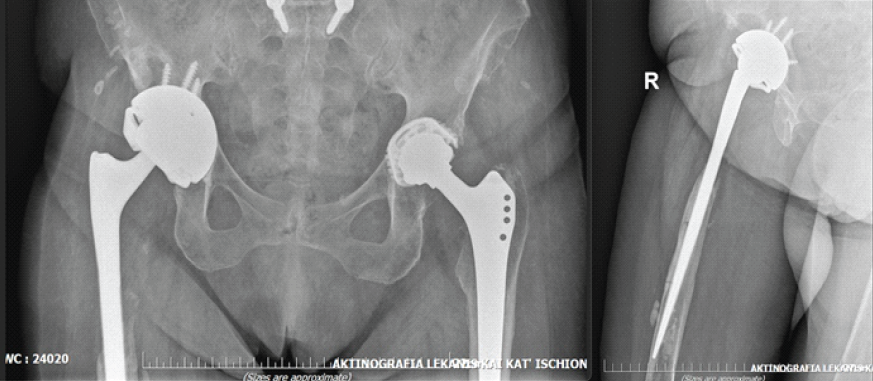

Six weeks after discharge, the patient sustained another prosthetic hip dislocation. She was admitted again, 4 months after the initial debridement, while still receiving oral fluconazole and trimethoprim–sulfamethoxazole. On readmission, pre-operative CRP was 2.68 mg/dL. A surgical intervention was decided upon. Similarly, a posterior hip approach was utilized. Intraoperatively, the acetabular component, ceramic head, bone cement, and screws were removed. A tantalum acetabular cup was implanted with five screws, coupled with a constrained polyethylene liner. The femoral stem was deemed stable intraoperatively and was therefore retained (Fig. 3). The ceramic head was replaced. The removed acetabular component was sent for sonication, and two drains were placed, which were retained for 7 days.

Figure 3: Hip dislocation in the setting of fungal periprosthetic joint infection, treated with acetabular cup revision.

Infectious disease specialists recommended oral trimethoprim–sulfamethoxazole (960 mg 3 times daily) for 4 weeks and oral fluconazole (200 mg twice daily) for 12 weeks. Immediately postoperatively, the patient remained hemodynamically stable and afebrile, requiring transfusion of one unit of packed red blood cells. Sonication of the retrieved acetabular component showed no microbial growth. On the 11th post-operative day, CRP had decreased to 4.61 mg/dL, and the wound appeared clean, without clinical signs of infection. The patient was discharged in good general condition.

The patient successfully completed the prescribed antimicrobial regimen. At both 6- and 12-month follow-up evaluations, she was seen at the outpatient clinic, where she demonstrated a well-healed surgical wound with no clinical or laboratory evidence of infection. At the latest follow-up, the patient was ambulatory with the aid of a cane and able to perform activities of daily living independently. She reported minimal discomfort in the right hip. Functional assessment using the Harris Hip Score yielded a value of 86, indicating good overall function. Despite the radiographic evidence of proximal femoral bone loss, the patient remained asymptomatic, reporting no pain or functional limitation. Given the absence of clinical symptoms, a conservative approach with close follow-up was elected. Should progressive pain or mechanical compromise develop in the future, reconstruction with a proximal femoral replacement (tumor-type prosthesis) would represent an appropriate surgical option (Fig. 4).

Figure 4: Pelvis anteroposterior (left) and right hip lateral (right) view at 12 months follow-up.